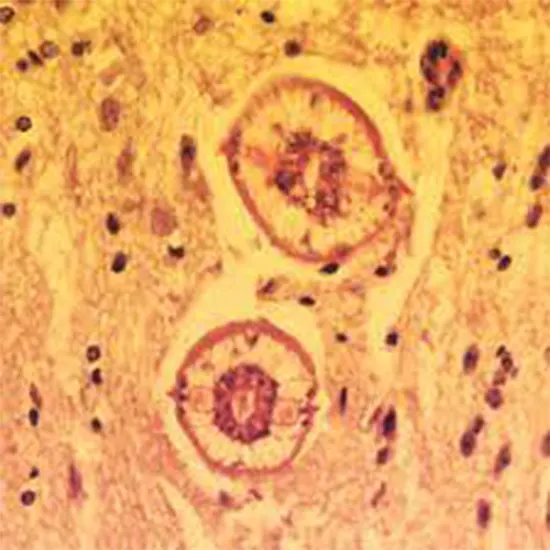

Baylisascaris infection, also known as Baylisascariasis, is a rare but serious parasitic infection caused by the roundworm Baylisascaris procyonis. This parasite primarily infects raccoons, and infection in humans can occur when individuals accidentally ingest the eggs of the parasite through contaminated soil, water, or food.

Diagnosis of Baylisascaris infection may be challenging, as the symptoms can be similar to other conditions. It is typically confirmed through a combination of clinical symptoms, history of exposure to raccoon-infested areas, and laboratory tests, such as serological testing, imaging studies, and examination of biopsy samples for detection of larvae.